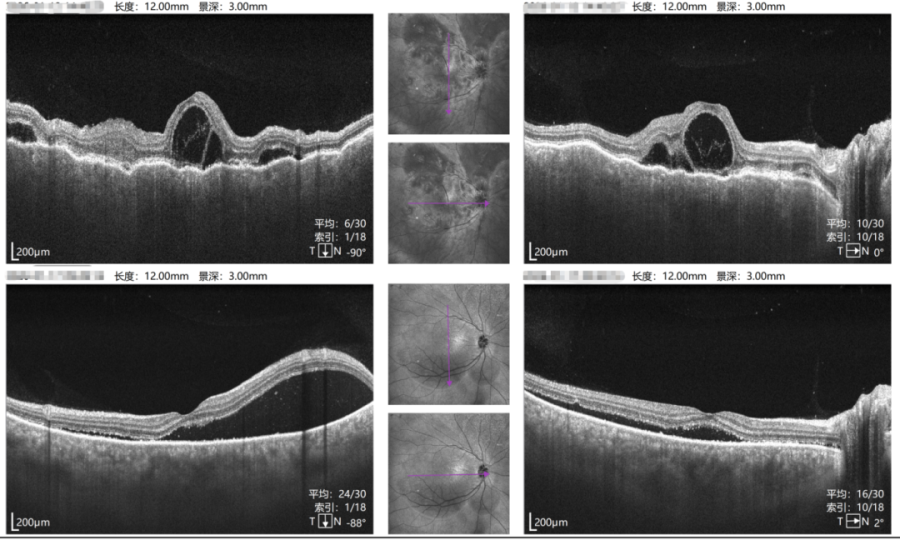

右眼治疗前后对比